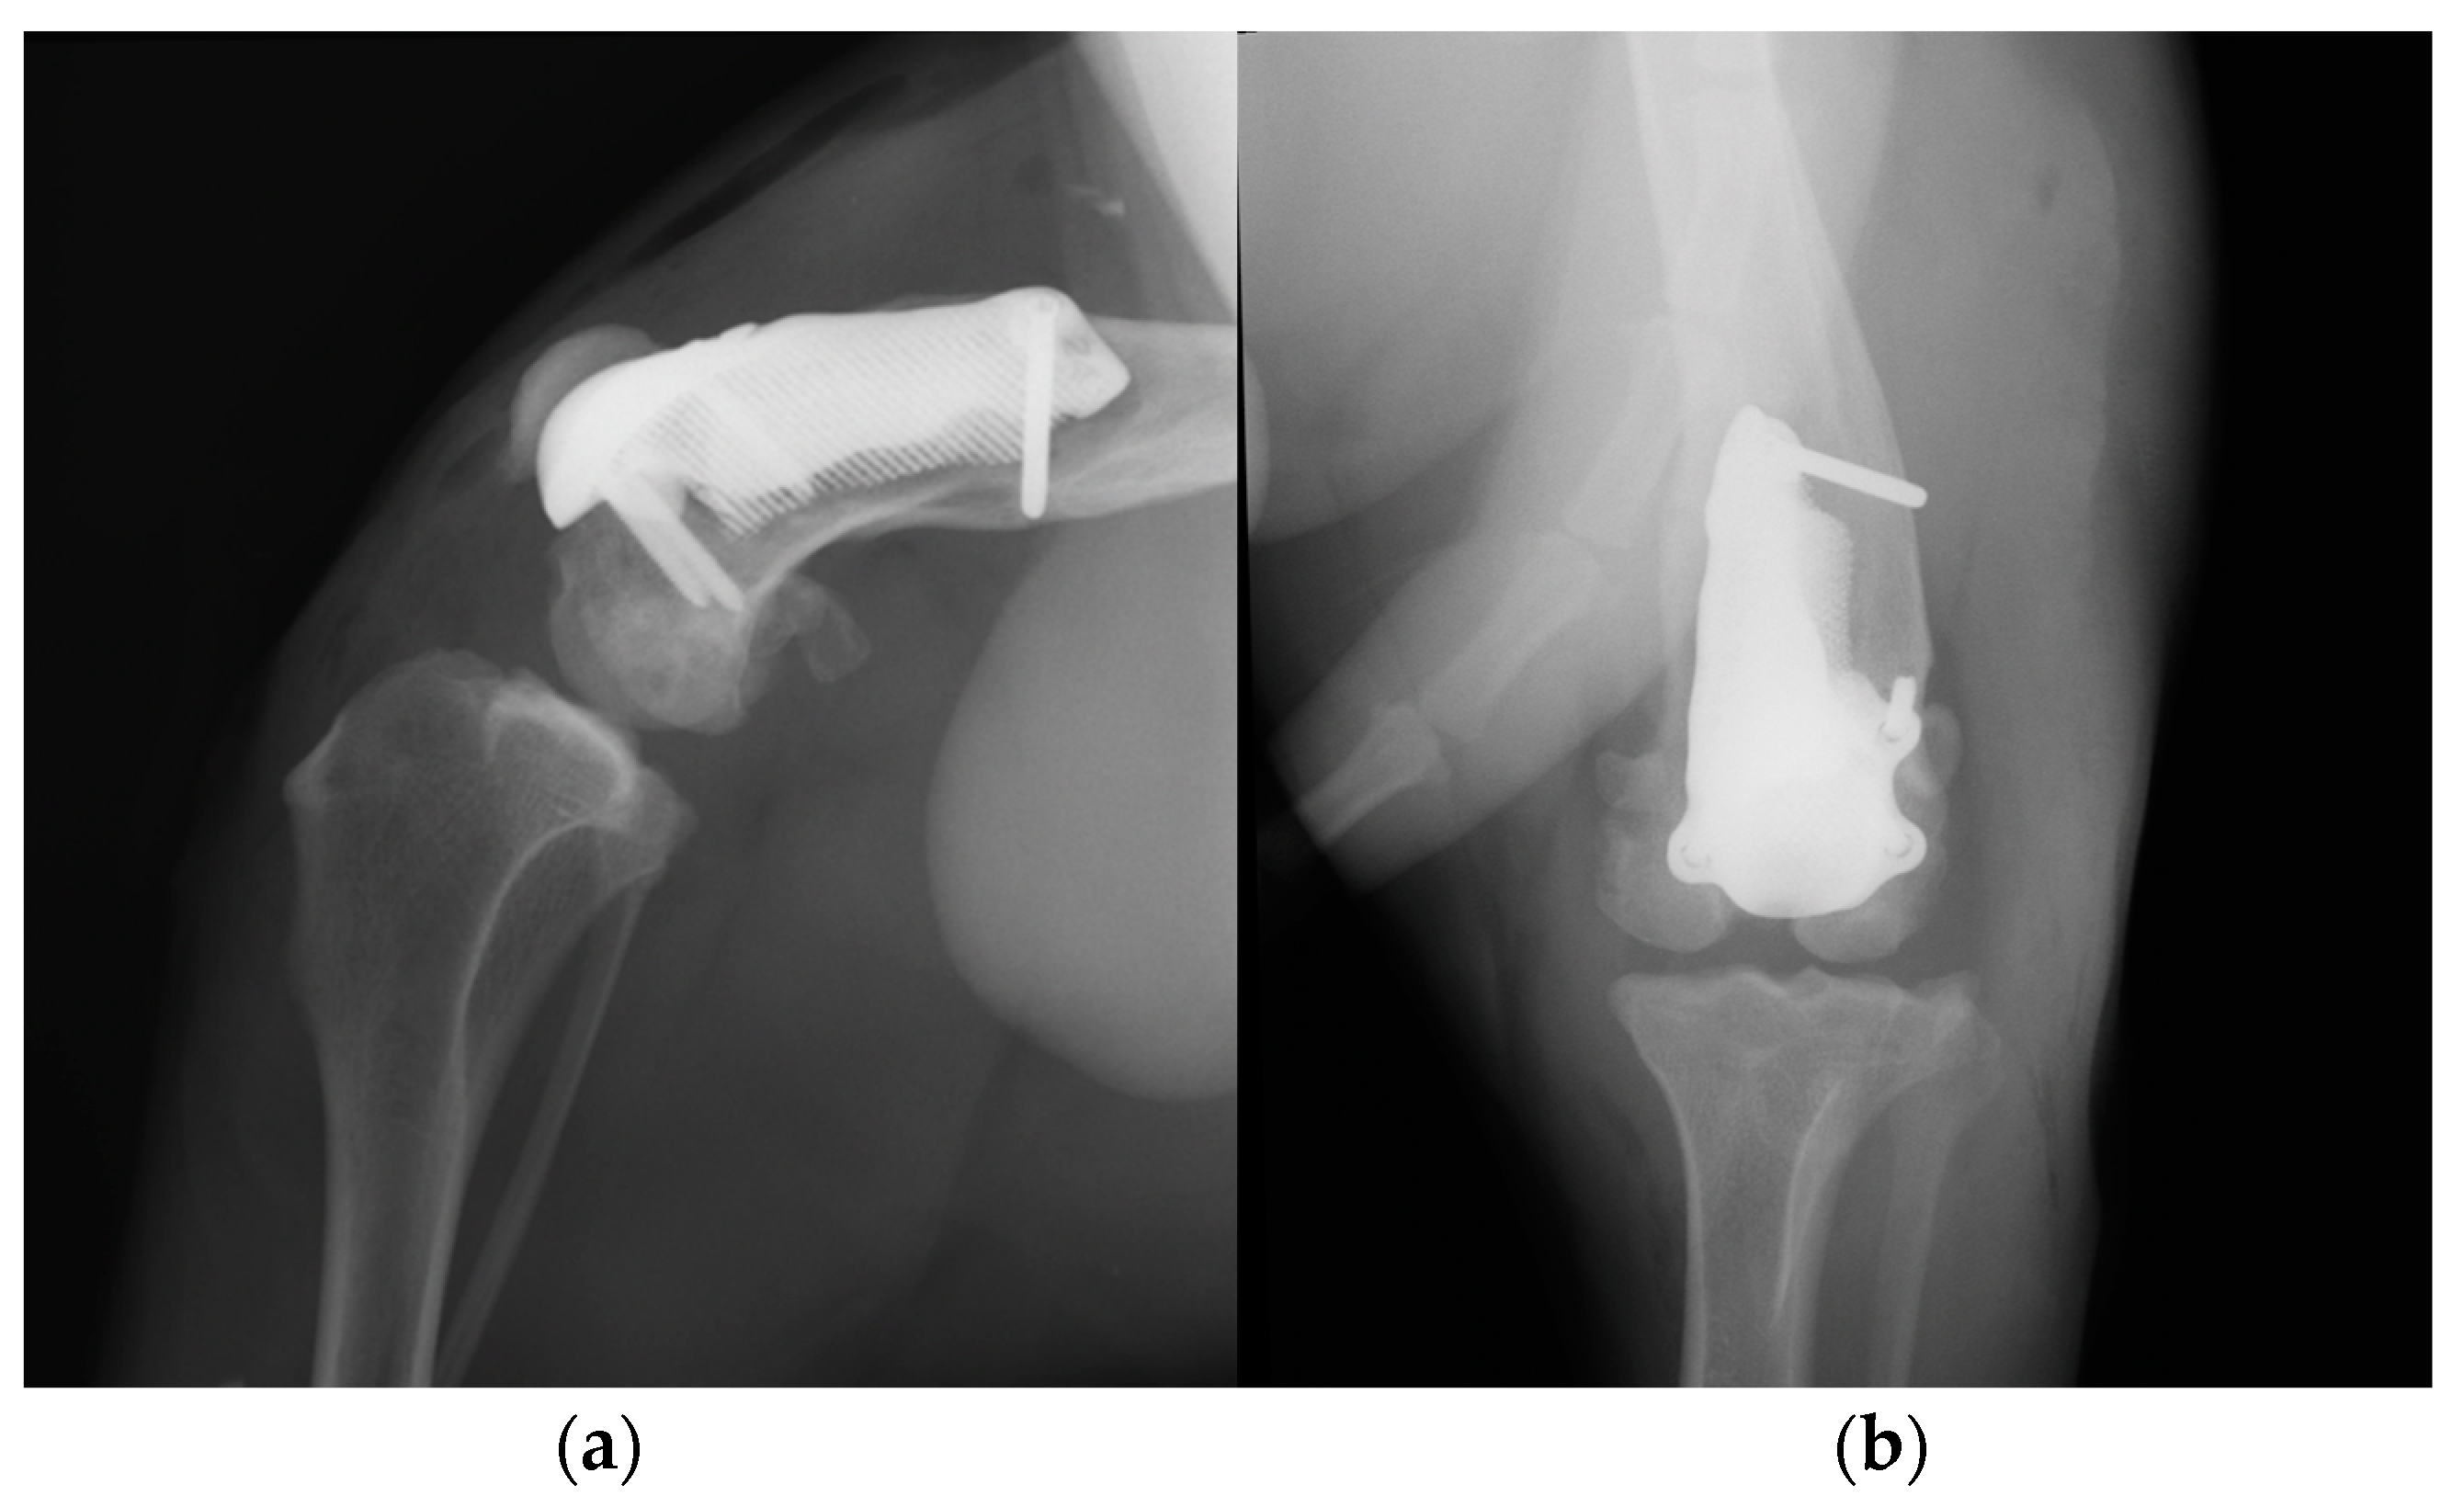

Postoperative medio-lateral and caudo-cranial radiographs of the stifle joint were performed to evaluate the proper prosthesis position, the length of the screws and to confirm the patellar reduction (Figure 10). To improve the postoperative assessment, CT scans of the right stifle joint were obtained. A modified Robert-Jones splint was applied for 24 hours postoperatively. Meloxicam (0,1 mg/kg) once a day and amoxicillin and clavulanic acid (20 mg/kg) twice a day were prescribed for 10 days and only short walks on the leash to be gradually increased during the two months post-operative rehabilitation was recommended.

Figure 10. Postoperative medio-lateral (a) and caudo-cranial (b) radiographs of the stifle joint showed the appropriate prosthesis position, the correct length of the screws and the reduction of the patella.